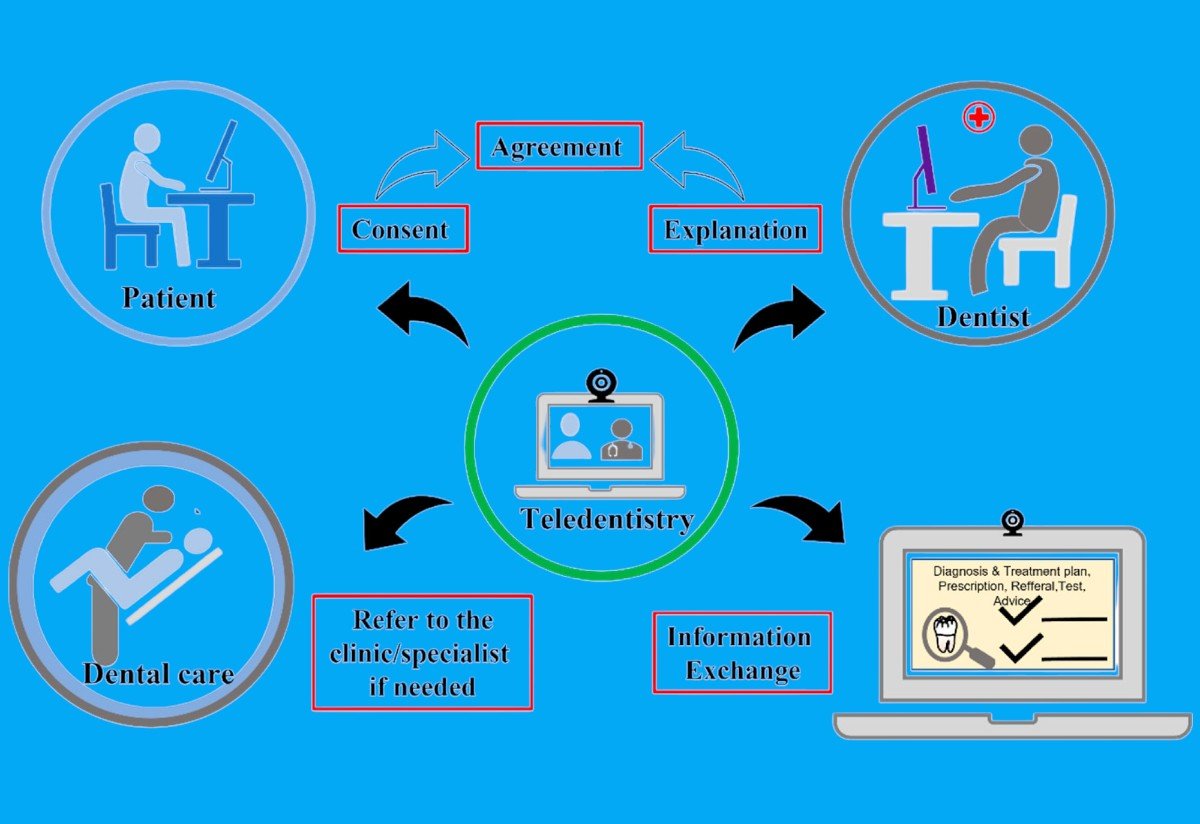

Запланируйте свой визит в режиме онлайн

Консультация врача 24/7